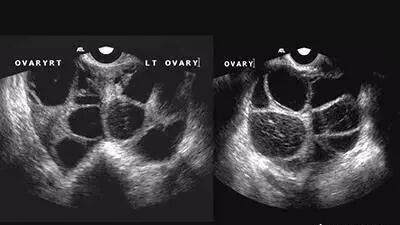

在采集卵子时,有些女性需要促排卵药物的帮助,但这类药物有两个非常严重的副作用:(1)卵巢过度刺激综合征(Ovarian Hyper-Stimulation Syndrome, OHSS),其严重症状的发生率约在0.4%-2%之间。主要症状是胸腹积水、卵巢囊性增大,同时还可能有脱水、血液的高凝状态(容易形成血栓)、肾衰竭、中风等严重的后果。